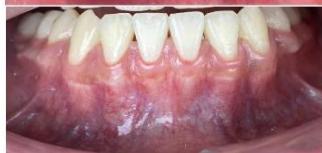

Figure 2: Pre-Treatment Intraoral Photographs

Intraoral examination revealed severe proclination and protrusion of both the maxillary and mandibular incisors [6]. The occlusal relationship was Class I at the canine (tooth 3) and first molar (tooth 6) levels bilaterally. A critical unfavorable biological factor was the proximity of the mandibular incisor roots to the labial cortical plate, representing a high-risk condition when planning extraction-based anterior retraction mechanics [10-12]. All four third molars were present.